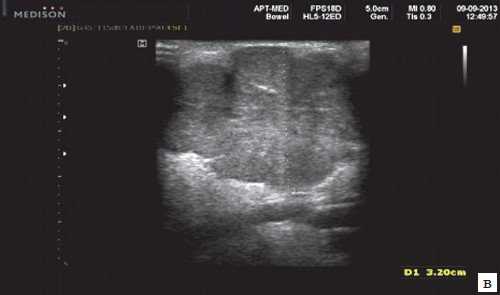

Сиаладениты - большая группа полиэтиологических воспалительных заболеваний СЖ (рис. 3). Первичные сиаладениты - сиаладениты, рассматриваемые в качестве самостоятельных заболеваний (например, эпидемический паротит). Вторичные сиаладениты - сиаладениты, являющиеся осложнениями или проявлениями других заболеваний (например, сиаладенит при гриппе). Эхографическая картина при разной этиологии малоспецифична. Этиология имеет клиническое значение в процессе определения тактики лечения.

Рис. 3. Сиаладенит правой поднижнечелюстной слюнной железы.